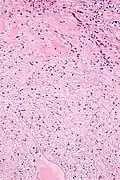

They consist of bland spindle-shaped or stellate-shaped cells in a loose stroma. Renal tubules may be entrapped.

High mag.

High mag.